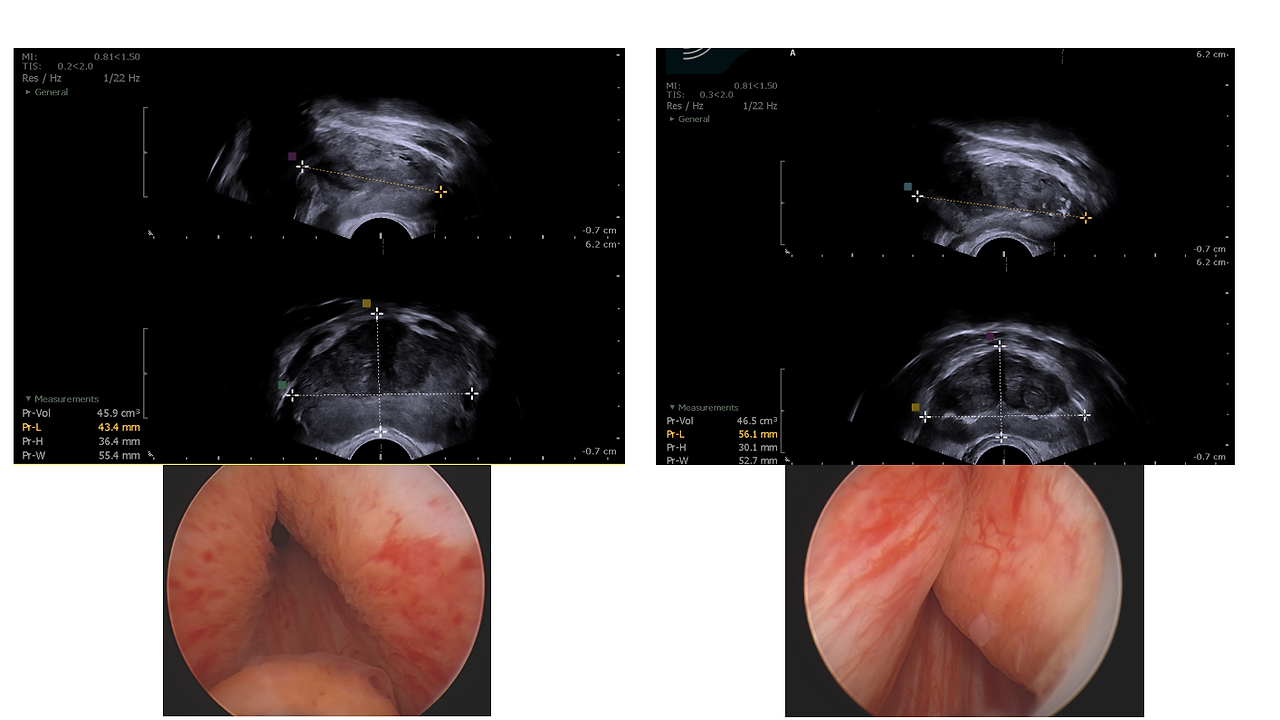

우리 몸은 수학 공식처럼 돌아가지 않습니다. 전립선이 60cc로 비대해졌음에도 소변을 보는 데 큰 지장이 없는 분이 있는가 하면, 겨우 30cc 남짓인데도 밤잠을 설치며 고통받는 분이 계십니다.

이 차이는 전립선이 '어디를 향해' 자라났느냐에서 결정됩니다. 사람의 얼굴이 제각각이듯 전립선의 관상도 다 다릅니다. 양옆으로 넓어진 것, 방광 쪽으로 툭 삐져나온 것, 혹은 요도 입구를 꽉 움켜쥐듯 자란 것까지. 단순히 부피가 크다고 해서 반드시 요도를 심하게 압박하는 것은 아닙니다. 결국 배뇨 장애의 본질은 '크기'라는 껍데기가 아니라, 요도를 막고 있는 '모양'이라는 실체에 있습니다.

결국 전립선 치료의 시작은 내 몸의 관상을 자세히 들여다보는 일입니다. 초음파와 내시경을 통해 내 전립선이 어떤 얼굴을 하고 있는지 확인하고, 비뇨의학과 전문의와 함께 '나만을 위한 지도'를 그려보시길 바랍니다.